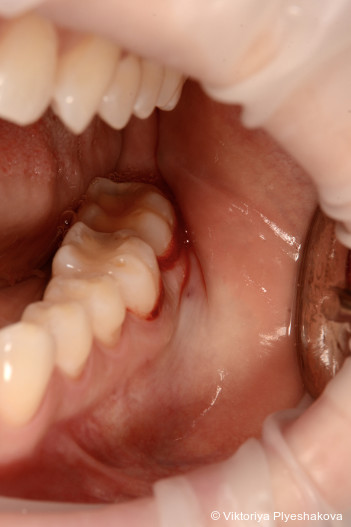

Die Patientin (ehemalige Raucherin) stand in den letzten Jahren unter erheblichem psychischem Stress. In dieser Zeit bemerkte sie eine deutliche Progression ihrer parodontalen Erkrankung. Sie hatte sich Monate zuvor einer nichtchirurgischen Parodontitistherapie sowie einer pa­rodontalen Lappenoperation im Bereich der Un­terkiefermolaren (46-47) unterzogen, die jedoch nur eine begrenzte Verbesserung gebracht hatten. Beim Sondieren wurde ein eitriger Ausfluss in den oberen Backenzähnen (17) festgestellt. Es zeigte sich generalisierte Plaque mit lokalisierten Zahnsteinablagerun­-gen. Die Pa­tientin war ansonsten allgemein gesund und hatte keine weiteren Beschwerden. Trotz der parodontalen Chirurgie in Regio 46 und 47 wurden lokalisiert erhöhte Sondierungstiefen von 6 bis 10 mm bei den Zähnen 17, 36-37 sowie 46-47 festgestellt. Inte­ressanterweise gab es keine Zahnbeweglichkeit außer Grad I bei Zahn 17. Zusätzlich wurde eine Furkationsbeteiligung Grad I bukkal an Zahn 17 beobachtet.

Periapikale Röntgenaufnahmen zeigten einen vertikalen/angulären Knochenverlust in den Regio­nen 16, 17, 36-37 und 46-47, der sich bis zum mittleren Drit­tel der Wurzeln erstreckte. Gemäß der Klassifikation der Parodontalerkrankungen von 2017 wurde eine lokalisierte Parodontitis – Sta­dium III (schwer), Grad C (schnelle Progression) diagnostiziert. Die Erkrankung war auf die Mola­renregionen mit Resttaschen > 6 mm begrenzt.